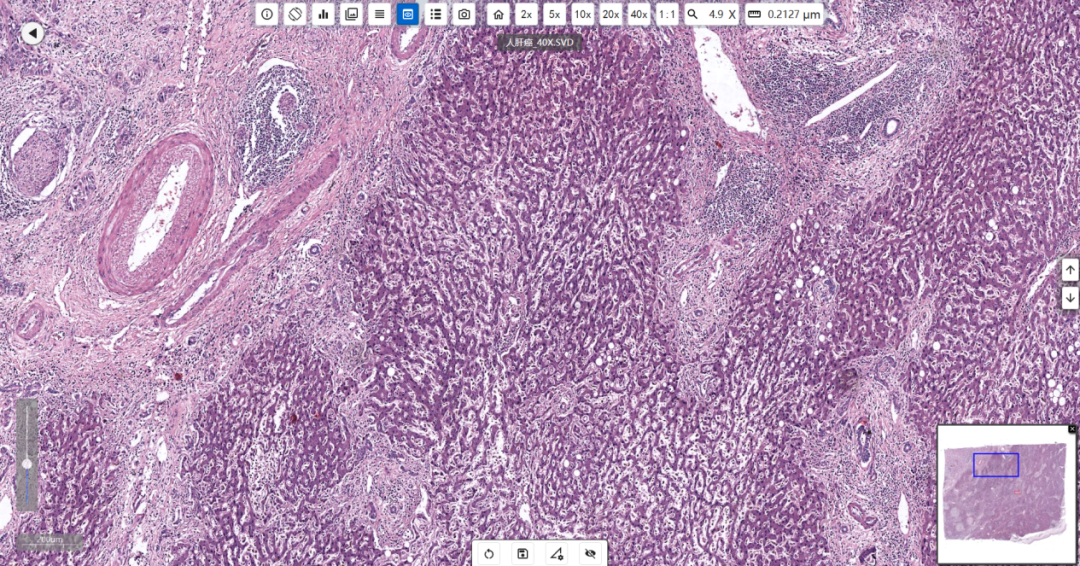

肝癌:肝臟的惡性腫瘤,其細胞來自肝臟的上皮組織,包括肝細胞和膽管細胞等。

明美切片掃描儀MDS4掃描的人肝癌切片